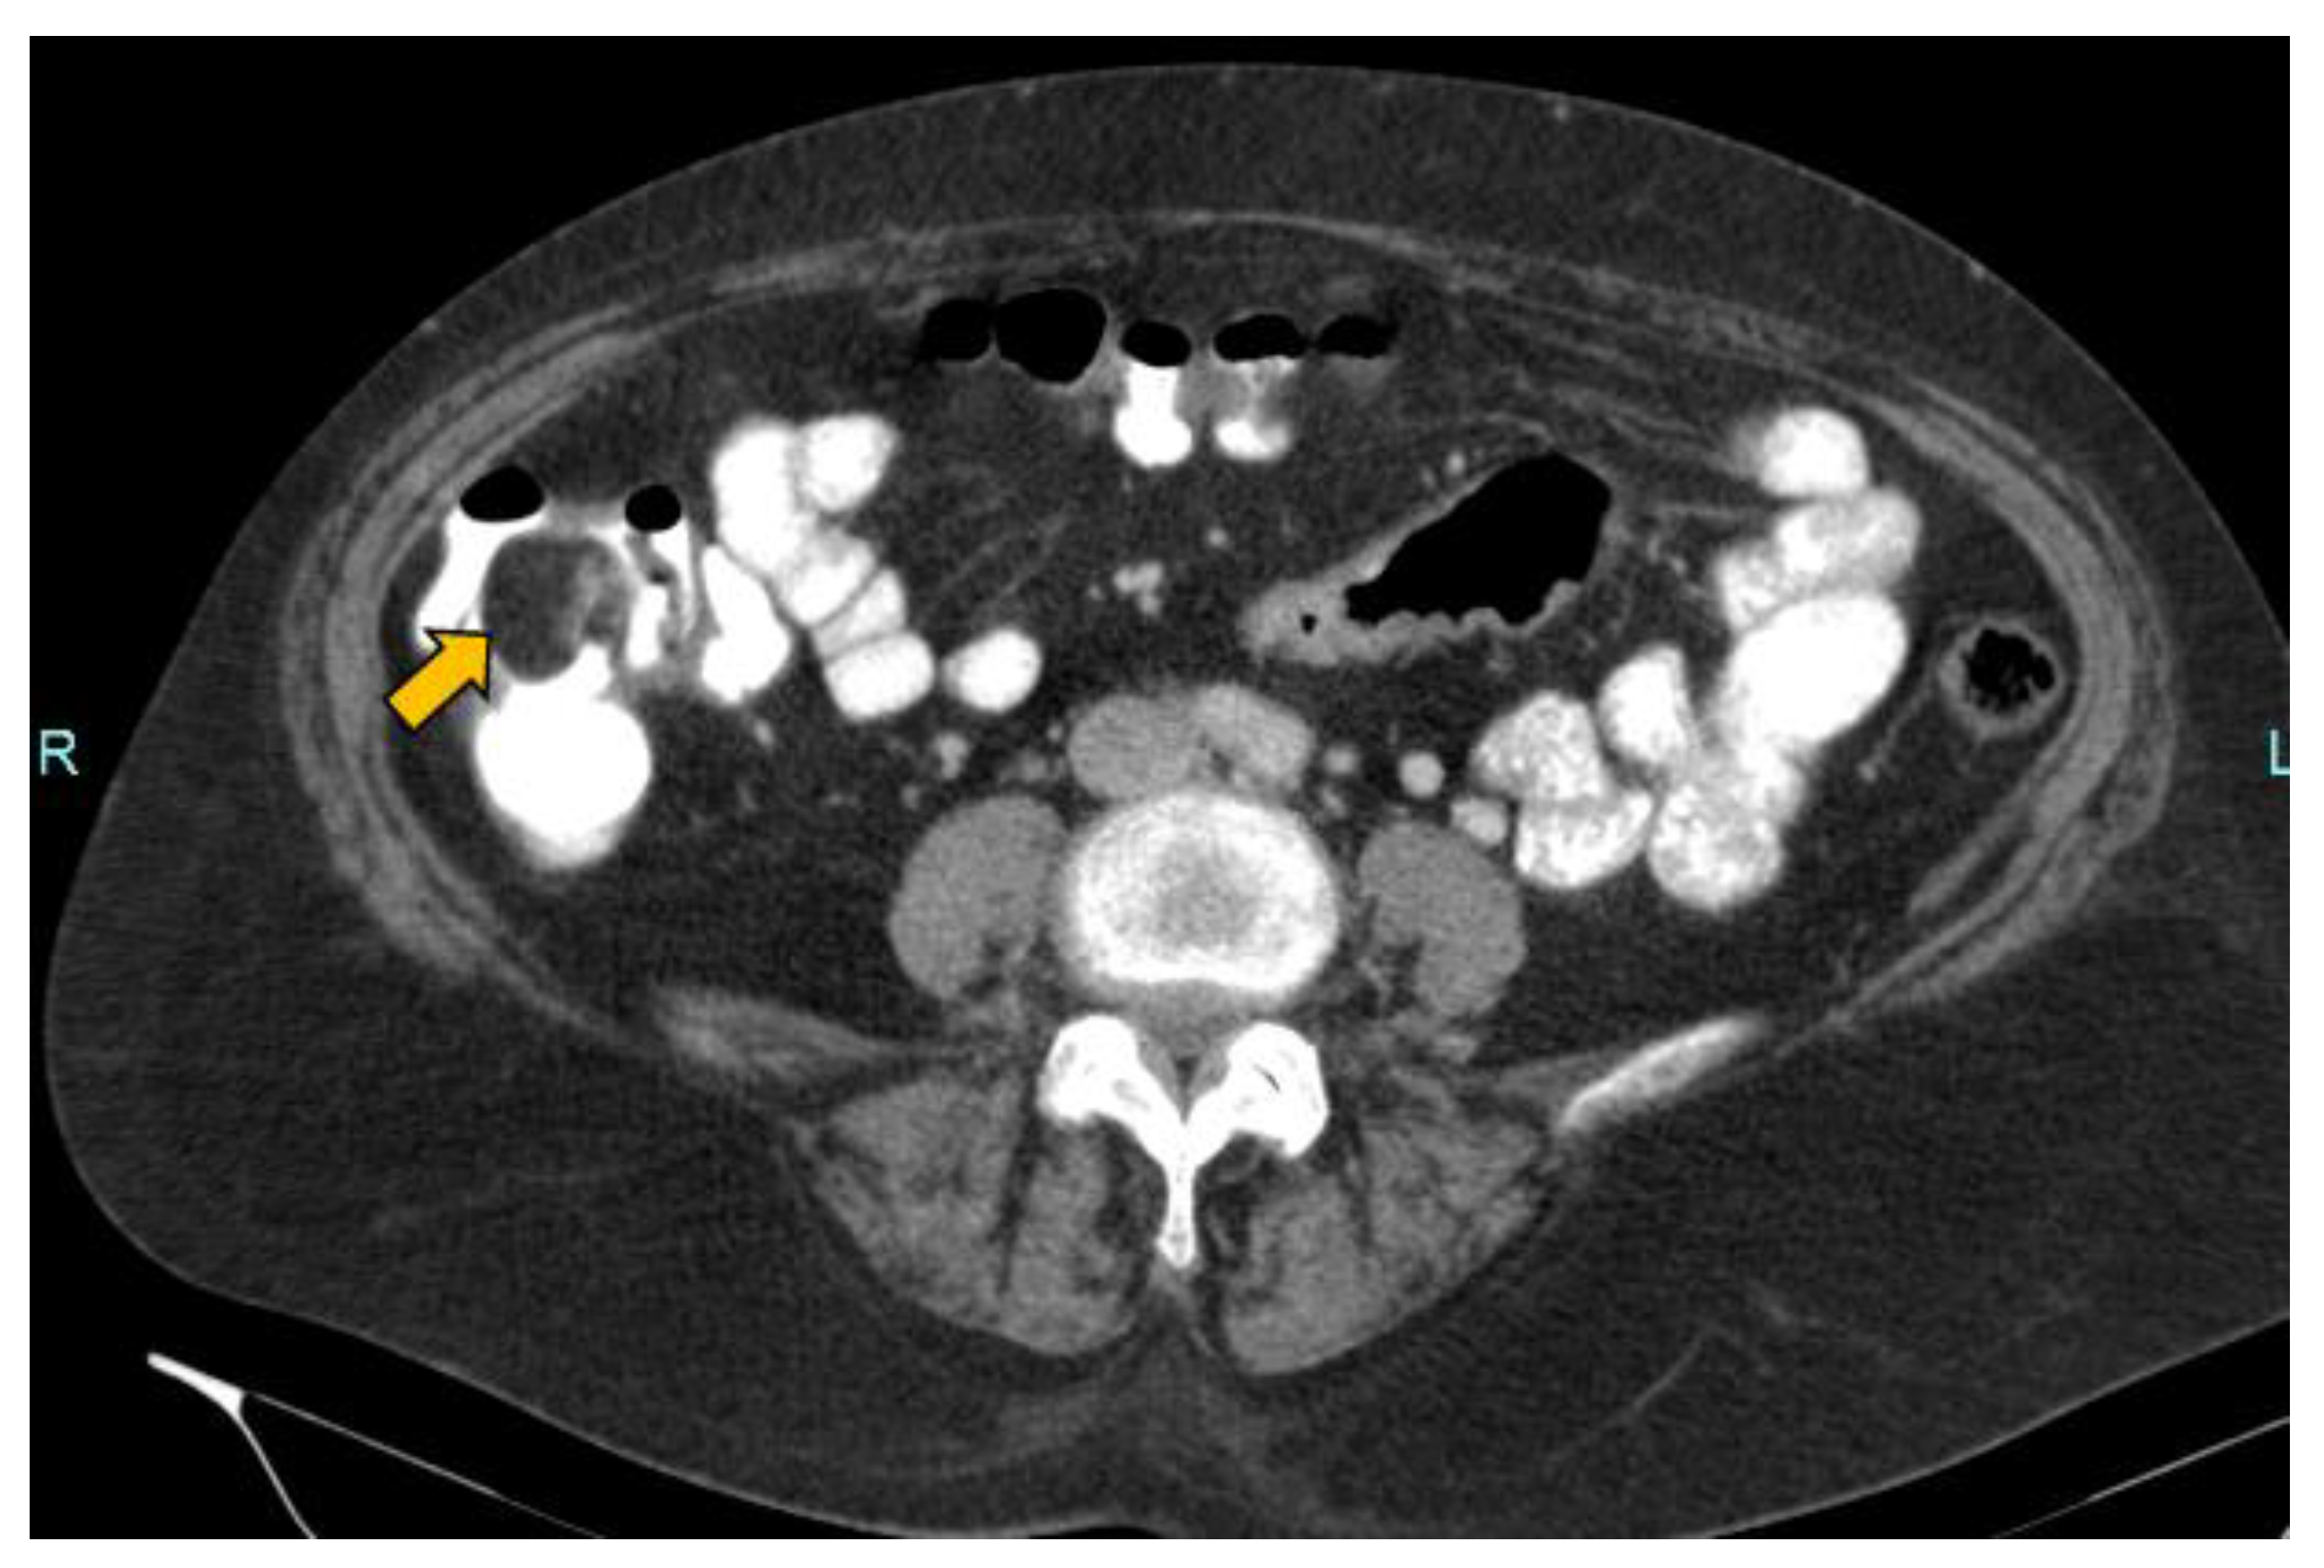

In our case, it was possible to follow up on the lipoma during biannual OCs performed because of her personal history of polyposis. Initially, it was proposed that abdominal-CT scans (Figure 1 and Figure 2) should be performed the year after each OC. This way, the size of the lesion could be monitored, and the degree of local infiltration could be determined. After the first abdominal-CT follow-up, to avoid exposure to radiation, HS (Figure 3) was included as an alternative to abdominal-CT. In the subsequent follow-up, in addition to the biannual OCs, two hydrocolonic ultrasound scans (without cleansing preparation) and one abdominal-CT scan were performed. During the seven years of follow-up, the lipoma remained stable, and the patient remains asymptomatic.

Figure 1.

Axial CT scan of the abdomen with intravenous and oral contrast showing the intracolonic lipoma in the caecum as a hypodense image (yellow arrow).

MR with fat saturation techniques can also be useful for detecting lipomas, but the detection of small lesions can be complicated [7]. The sensitivity of MR in the detection of fat composition is 100% [1]. Lipomas are easily distinguishable using abdominal-CT, as they appear as well-defined hypodense lesions between −40 and −120 Hounsfield units [36] (Figure 1 and Figure 2). The sensitivity of abdominal-CT in the detection of lipomas is 58–100%, and they have a characteristic image that looks like a “target sign” or “doughnut sign” [5,37]. Abdominal-CT is a very useful technique in urgent cases, but for follow-up, it presents problems due to the associated radiation. In addition, local infiltration can be difficult to exclude using abdominal-CT or MR [1].